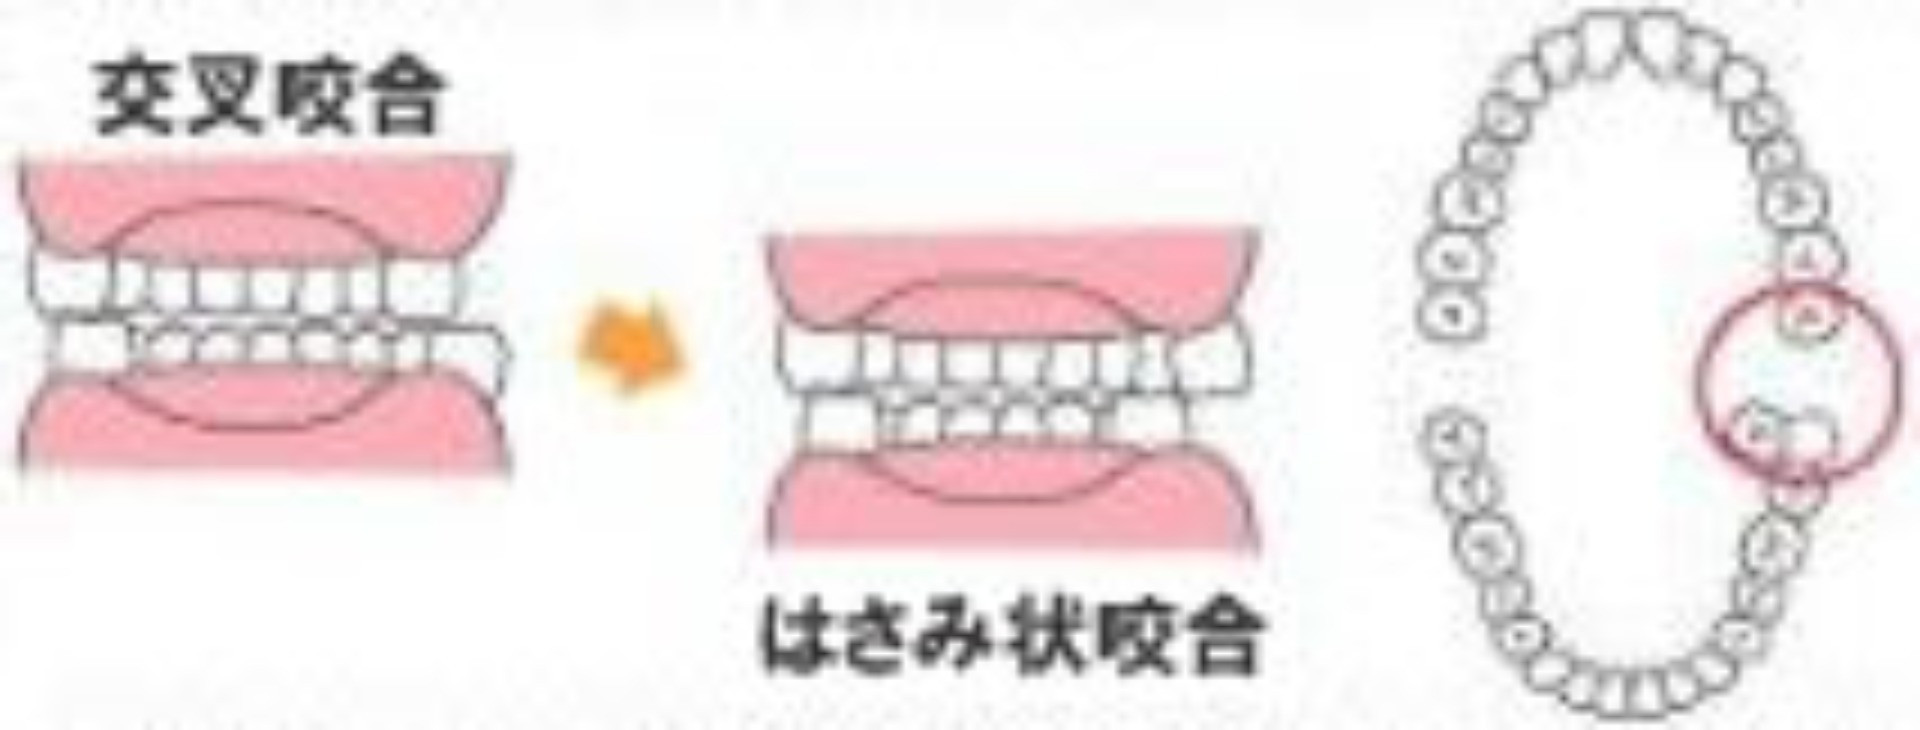

交叉咬合はこうしてなる・こうして防ぐ

クロスバイトとも言われます。 クロスバイトとも言われます。

上下の奥歯が横にずれている噛み合わせです。

本来なら下の奥歯より外になるはずの上の奥歯が内側になっているのが交叉咬合ですが、奥歯が完全にすれ違うと「はさみ状咬合(シザーズバイト」となってしまいます。これではうまく噛めません。 |